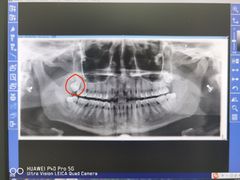

• 上海市杨浦区牙病防治所

• -上海市杨浦区牙病防治所